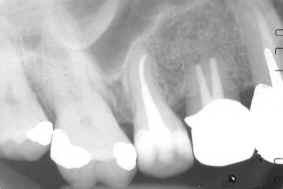

Deciding which one is appropriate for you will require a physical examination and an X-Ray or two.

X-rays

During a root canal treatment, your dentist will need to take X-ray images of the tooth to determine the position of the instruments and filling material inside the root canals. An electronic “apex locator” may also be used in determining the length of the root canals.